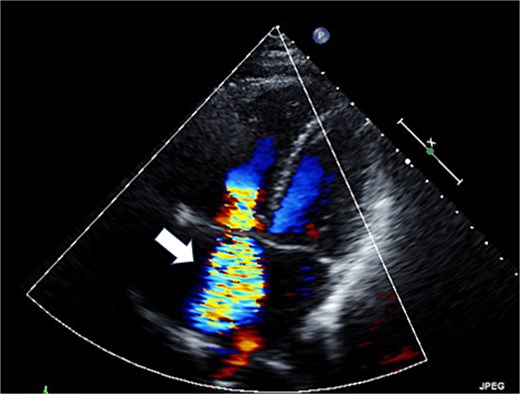

The patient was a 50-year-old female with pulmonary (PV) and tricuspid valve (TV) regurgitation. At 8 years old, she received RVOT reconstruction due to PV stenosis. When she was 44 years old, transthoracic echocardiography revealed PV regurgitation and PVR (INSPIRIS 19 mm; Edwards Lifesciences Corporation, Irvine, CA, USA) and tricuspid annuloplasty (Physio annuloplasty ring 28 mm; Edwards Lifesciences, Irvine, CA, USA) was performed. After 3 years of this operation, she gradually became complained of palpitation and syncope. Transthoracic echocardiography revealed severe tricuspid regurgitation due to leaflet tethering and moderate pulmonary regurgitation caused by dysfunction of one of the tissue valve leaflets (Figs 1 and 2). Cardiac magnetic resonance imaging showed right ventricular enlargement (right ventricular end-diastolic volume index; 97.5 ml/m2). Finally, we decided to perform a redo PV and TV replacement.

Preoperative transthoracic echocardiography: severe tricuspid regurgitation. The regurgitant jet is indicated by the white arrow.